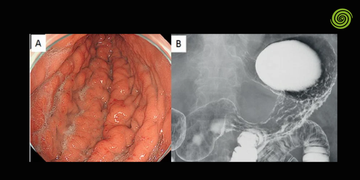

Visualización en tiempo real

La cámara del endoscopio transmite imágenes a un monitor médico en alta definición.

El especialista observa estas imágenes mientras controla el movimiento del instrumento para examinar las diferentes áreas del órgano.

El sistema óptico permite capturar imágenes del interior del cuerpo.

En los equipos actuales, la imagen se obtiene mediante sensores digitales que transmiten la señal al procesador de video.

La calidad de este sistema determina la nitidez de la imagen y la capacidad de detectar lesiones pequeñas.

Estos avances han mejorado la capacidad de detectar lesiones tempranas en el tracto digestivo.

En hospitales que realizan diagnóstico avanzado, la calidad de imagen es un factor determinante para identificar cambios sutiles en la mucosa digestiva.